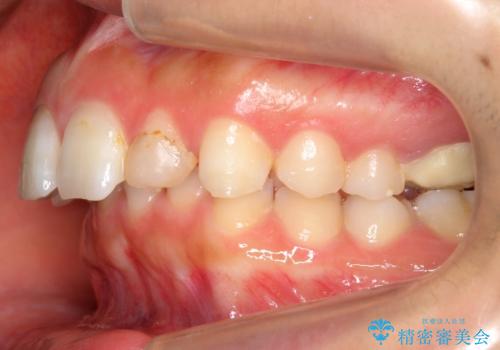

出っ歯を治したい 過蓋咬合

- 出っ歯を主訴に来院。

かみ合わせが深く、治療に時間がかかりました。

上顎2番は矮小歯だったのをセラミックで被せています。

口唇の突出感がなくなり、理想的な横顔になりました。